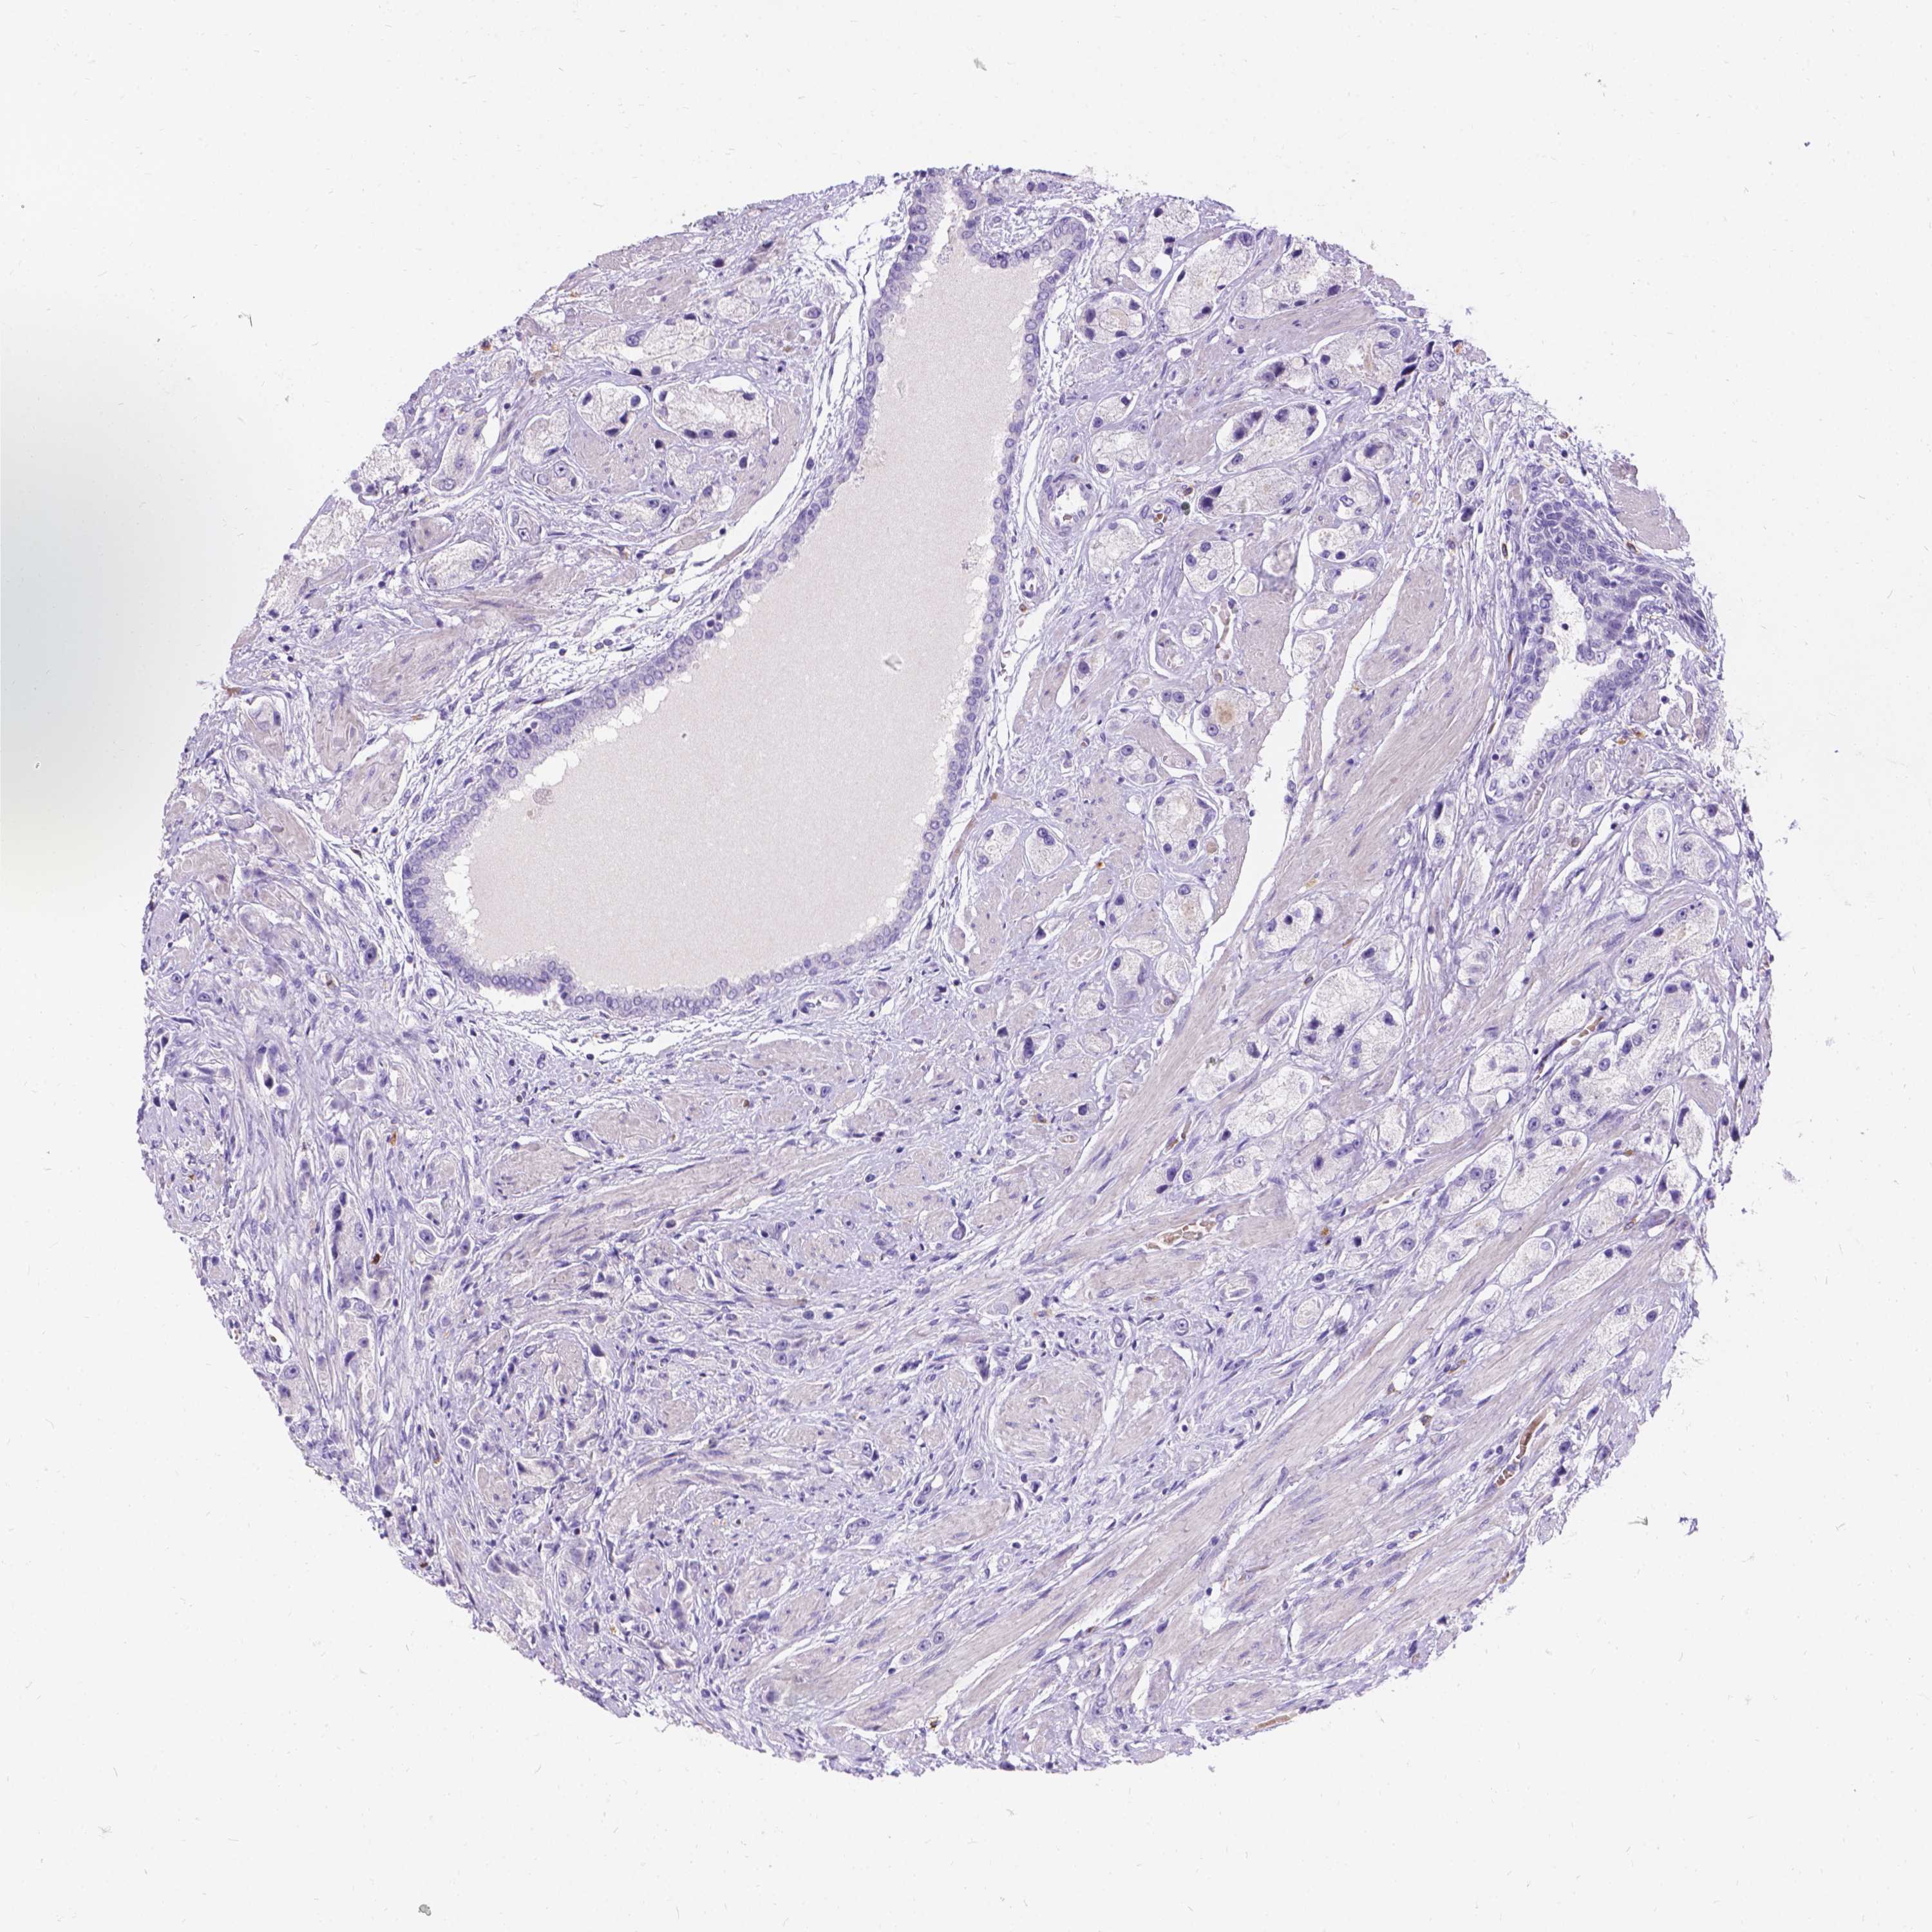

PROSTATE CANCER - Protein expressioni

A mouse-over function shows sample information and annotation data. Click on an image to view it in a full screen mode. Samples can be filtered based on level of antibody staining by selecting one or several of the following categories: high, medium, low and not detected. The assay and annotation is described here.

Note that samples used for immunohistochemistry by the Human Protein Atlas do not correspond to samples in the TCGA dataset.

Antibody stainingi

Antibody staining in the annotated cell types in the current human tissue is reported as not detected, low, medium, or high, based on conventional immunohistochemistry profiling in selected tissues. This score is based on the combination of the staining intensity and fraction of stained cells.

Each image is clickable and will lead to virtual microscopy that enables deeper exploration of all samples and also displays staining intensity scores, fraction scores and subcellular localization as well as patient and tissue information for each sample.

Antibody HPA013424

Staining

High

Medium

Low

Not detected

Intensity

Strong

Moderate

Weak

Negative

Quantity

>75%

75%-25%

<25%

None

Location

Nuclear

Cytoplasmic/membranous

Cytoplasmic/membranous,nuclear

Adenocarcinoma, High grade

Adenocarcinoma, Low grade